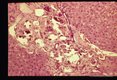

Eggs in armadillo (Dasypus novemcinctus) liver.

Heterobilharzia...